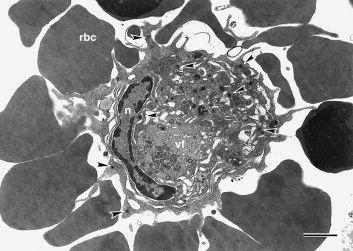

图:对非洲猪瘟病毒马拉维分离株感染的肺泡巨噬细胞的血液吸收。红细胞(rbc)粘附在感染细胞的表面,产生经典的莲座丛。病毒结构包括在组装的各个阶段含有病毒颗粒的核周病毒工厂(vf)和在通过出芽离开细胞之前的细胞质病毒(箭头)。细胞核(n)。条形代表5μm。(图源:SM Brookes)